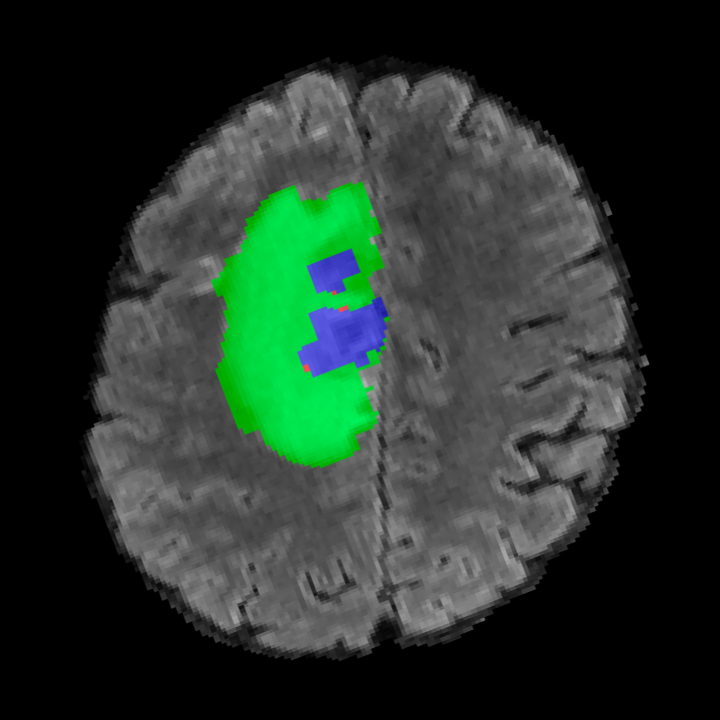

![]() |

|||

Tumour Information Preservation. For the brain tumor segmentation, we use a Swin UNETR model[28, 70], trained with random rotation, and intensity as data augmentation. On the test set with human ground-truth annotations (), the brain volumes generated from single slice input preserve the volume of the different tumour components (paired t-test, for all 3 classes). In Figure 4, we highlight the tumor profiles of the generated MRIs compared to the ground truth tumour profile. The real MRI Dice score in the test set is 85.15 while the generated MRIs from a single slice have a dice score of 83.09. This shows how the generated MRIs indeed preserve the tumor information and can act as an affordable and informative pseudo-MRI, before conducting an actual costly MRI examination in hospitals. More detailed results are provided in supplementary material.